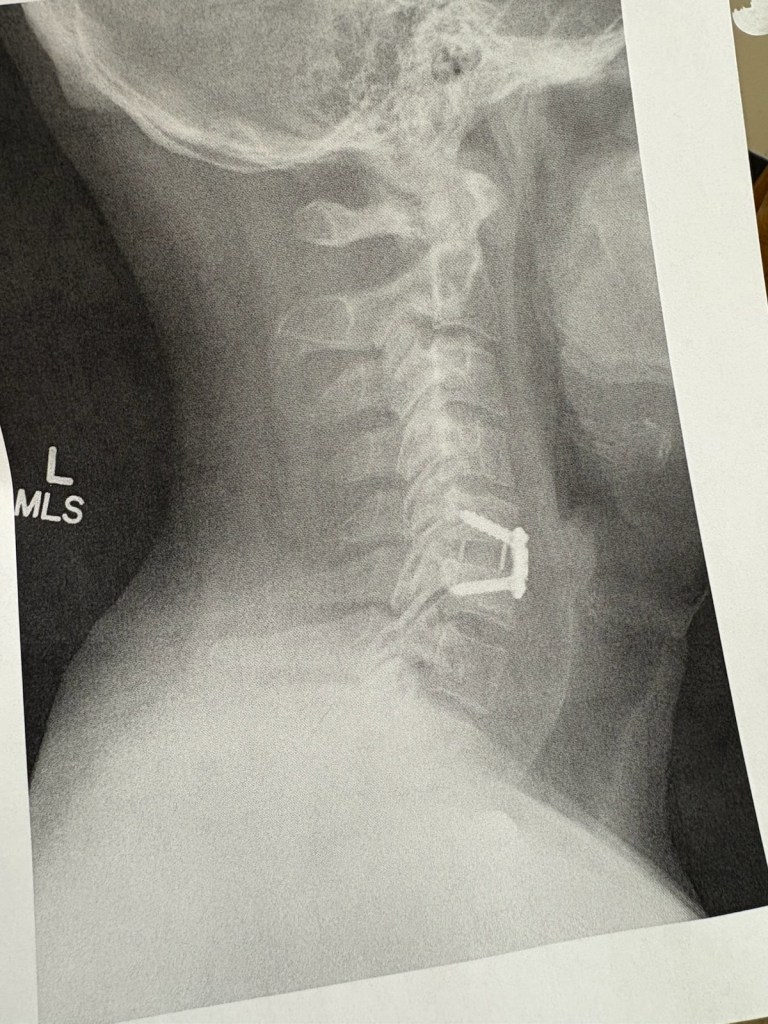

What most of you don’t know is I spent most of the year dealing with a herniated disk in my neck, and I had to take three different nerve block injections to get through the season. I ended up scheduling surgery on Oct. 28. I also fished another league this year and our season was supposed to be over before then. The last event in Florida was postponed because of Hurricane Helene and eventually rescheduled for Dec. 10 for Lake Murray.

The surgery involved some screws and replacing a bad disk. While I’m still sore in my shoulder and down my back from the surgery, the feeling in my hands has returned. Now I can focus on getting myself ready for the upcoming season.